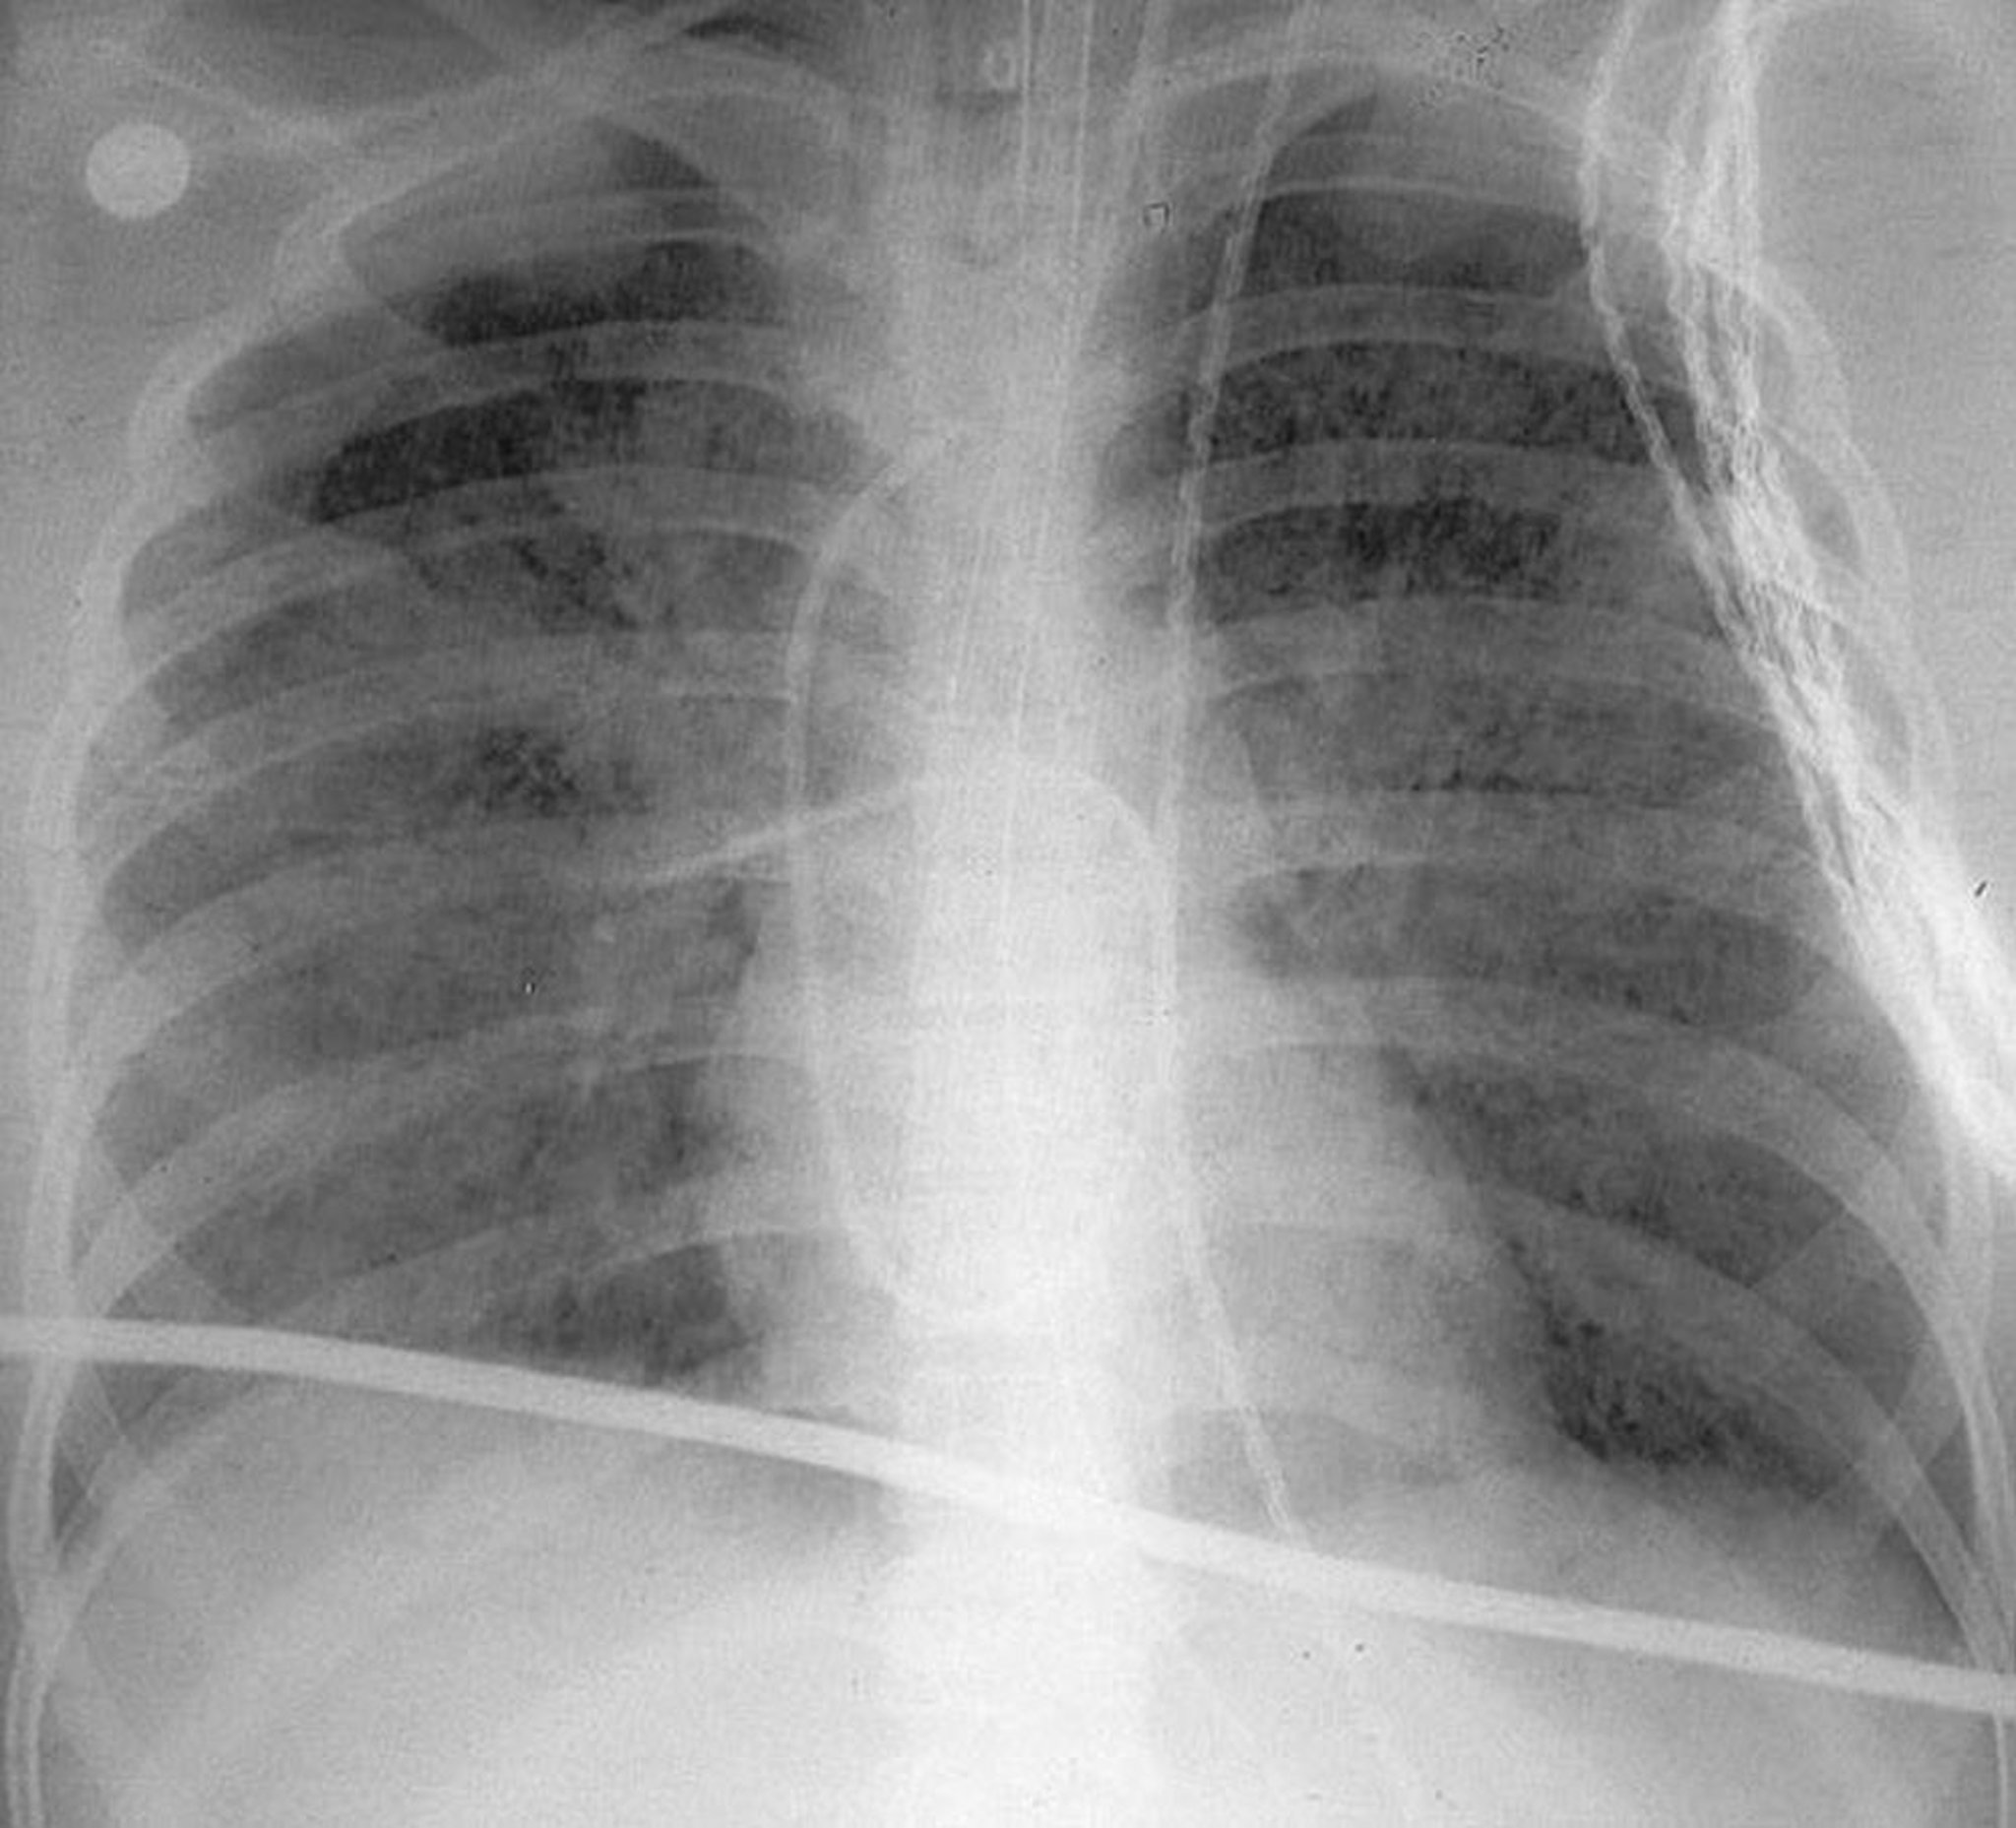

急性呼吸窮迫症候群

この立位胸部X線写真上では,急性呼吸窮迫症候群(ARDS)に特徴的なびまん性かつ両側性の透過性低下がみられる。